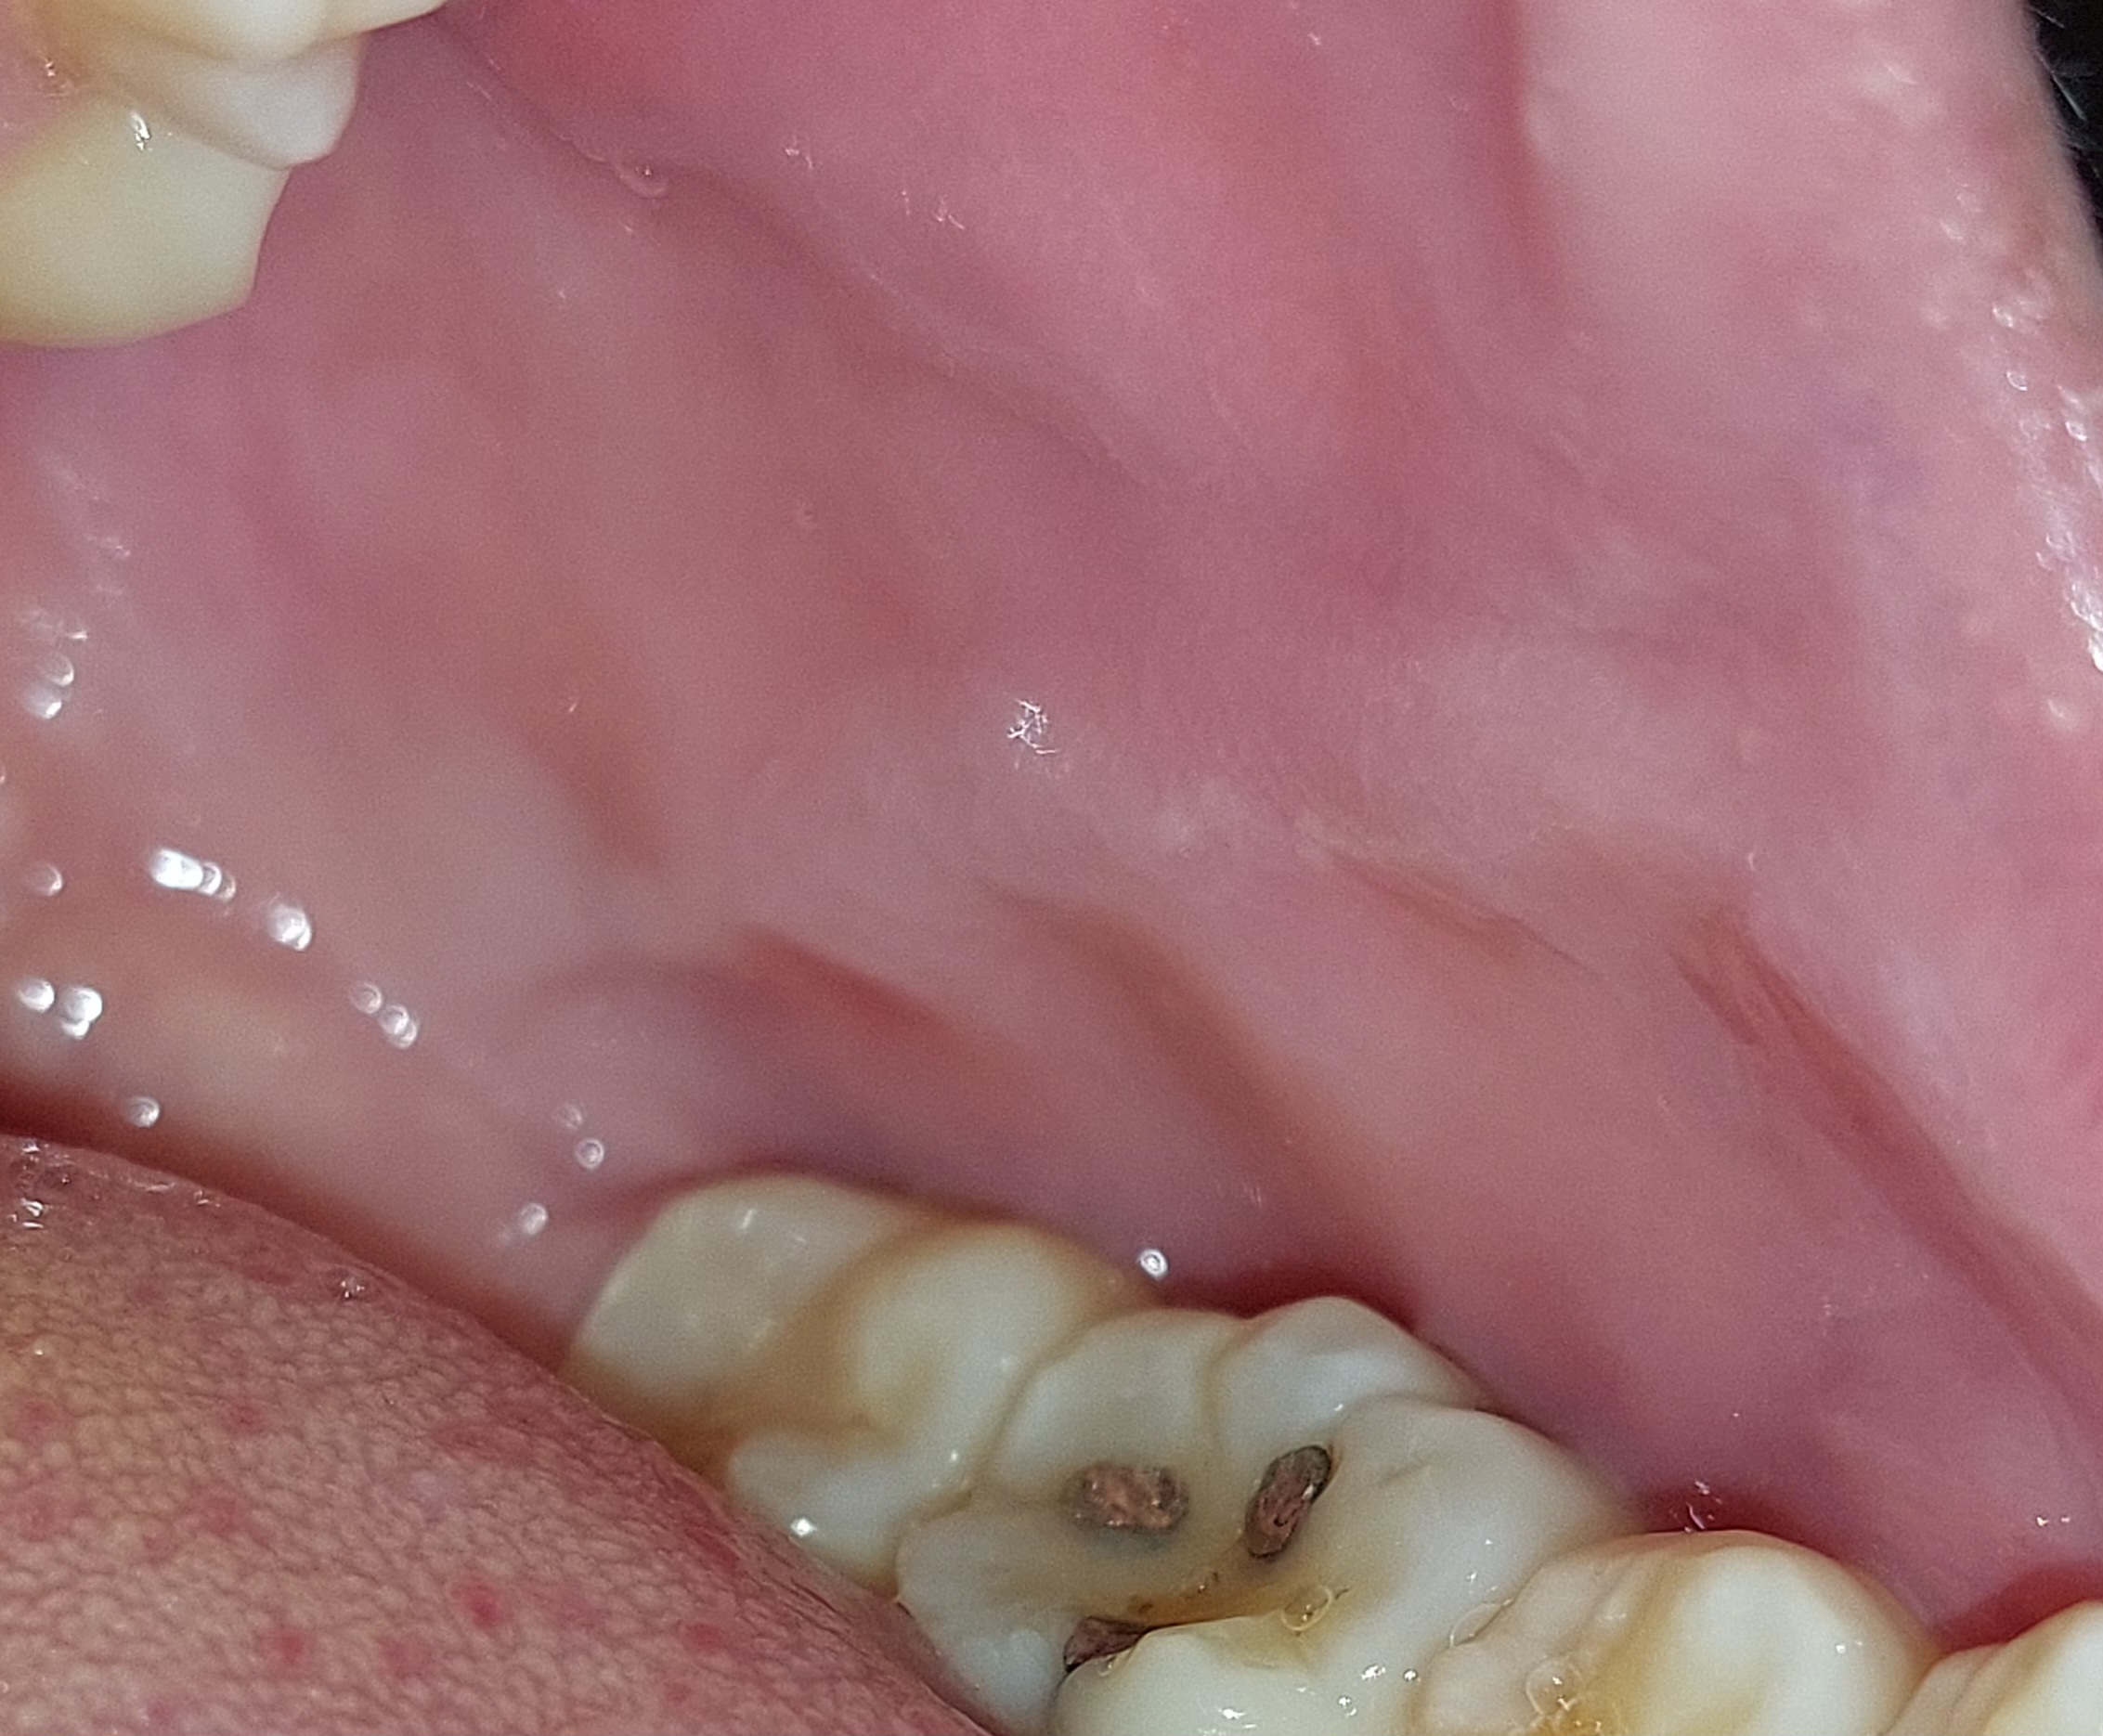

ต่อมาพบว่า ใต้ลิ้นด้านข้างและกระพุ้งแก้ม มีลักษณะ ขาวๆ ยาวๆ แต่ไม่เป็นแผ่นแข็ง มีตุ่มเล็กๆ ร่วมด้วย ข้างใต้ลิ้นเป็นคราบขาว แปรงแล้วก็กลับมาเป็นอีก ช่วงหลังเริ่มกังวลว่าอาจเป็น เชื้อราในปาก (oral thrush) หรือ oral hairy leukoplakia เป็นๆ หายๆ มานานกว่า 3 เดือนแล้วค่ะ

ขอบคุณคุณหมอล่วงหน้าค่ะ ???? (รูปที่แนบ)

ลักษณะไม่เหมือนเชื้อราครับ เหมือนจะแพ้อะไรบางอย่าง ควรไปพบแพทย์ หู คอ จมูก ให้ตรวจและรักษาจะดีกว่าครับ ดูจากรูปเห็นไม่ชัด ไม่เหมือนกับของจริงครับ